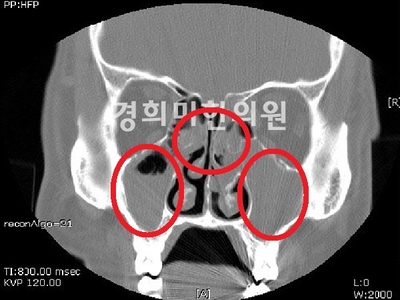

부비강염 CT이미지

편도염 만약 급성 비염의 카타르기가 지나 2차 세균 감염이 되면 끈적끈적한 노란 콧물과 함께 코가 막혀서 후비루가 심해집니다.더 악화되면 부비강염, 중이염, 인두편도염, 기관지염, 폐렴, 장염 등의 합병증이 동반될 수 있습니다.이러한 합병증은 면역력이 저하된 환자나 어린이에게 잘 나타나므로 주의가 필요합니다.